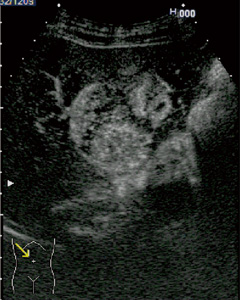

■ Wideband Pulse Inversion(WPI)(図2)

気泡である超音波造影剤ソナゾイドは,送波音圧を低めに設定することで超音波による気泡の破壊を極力低減し,気泡からの反射波に含まれるハーモニック成分を画像化する。WPIは,従来のPulse Inversion法より低周波成分を強調しつつ,効率良くハーモニック成分を抽出する手法で,これにより高感度とペネトレーションの改善を図っている。

図2 オルタネートモード (画像ご提供:三重大学 田中秀明先生)

a:WPI像

b:LowMIでのFundamental像